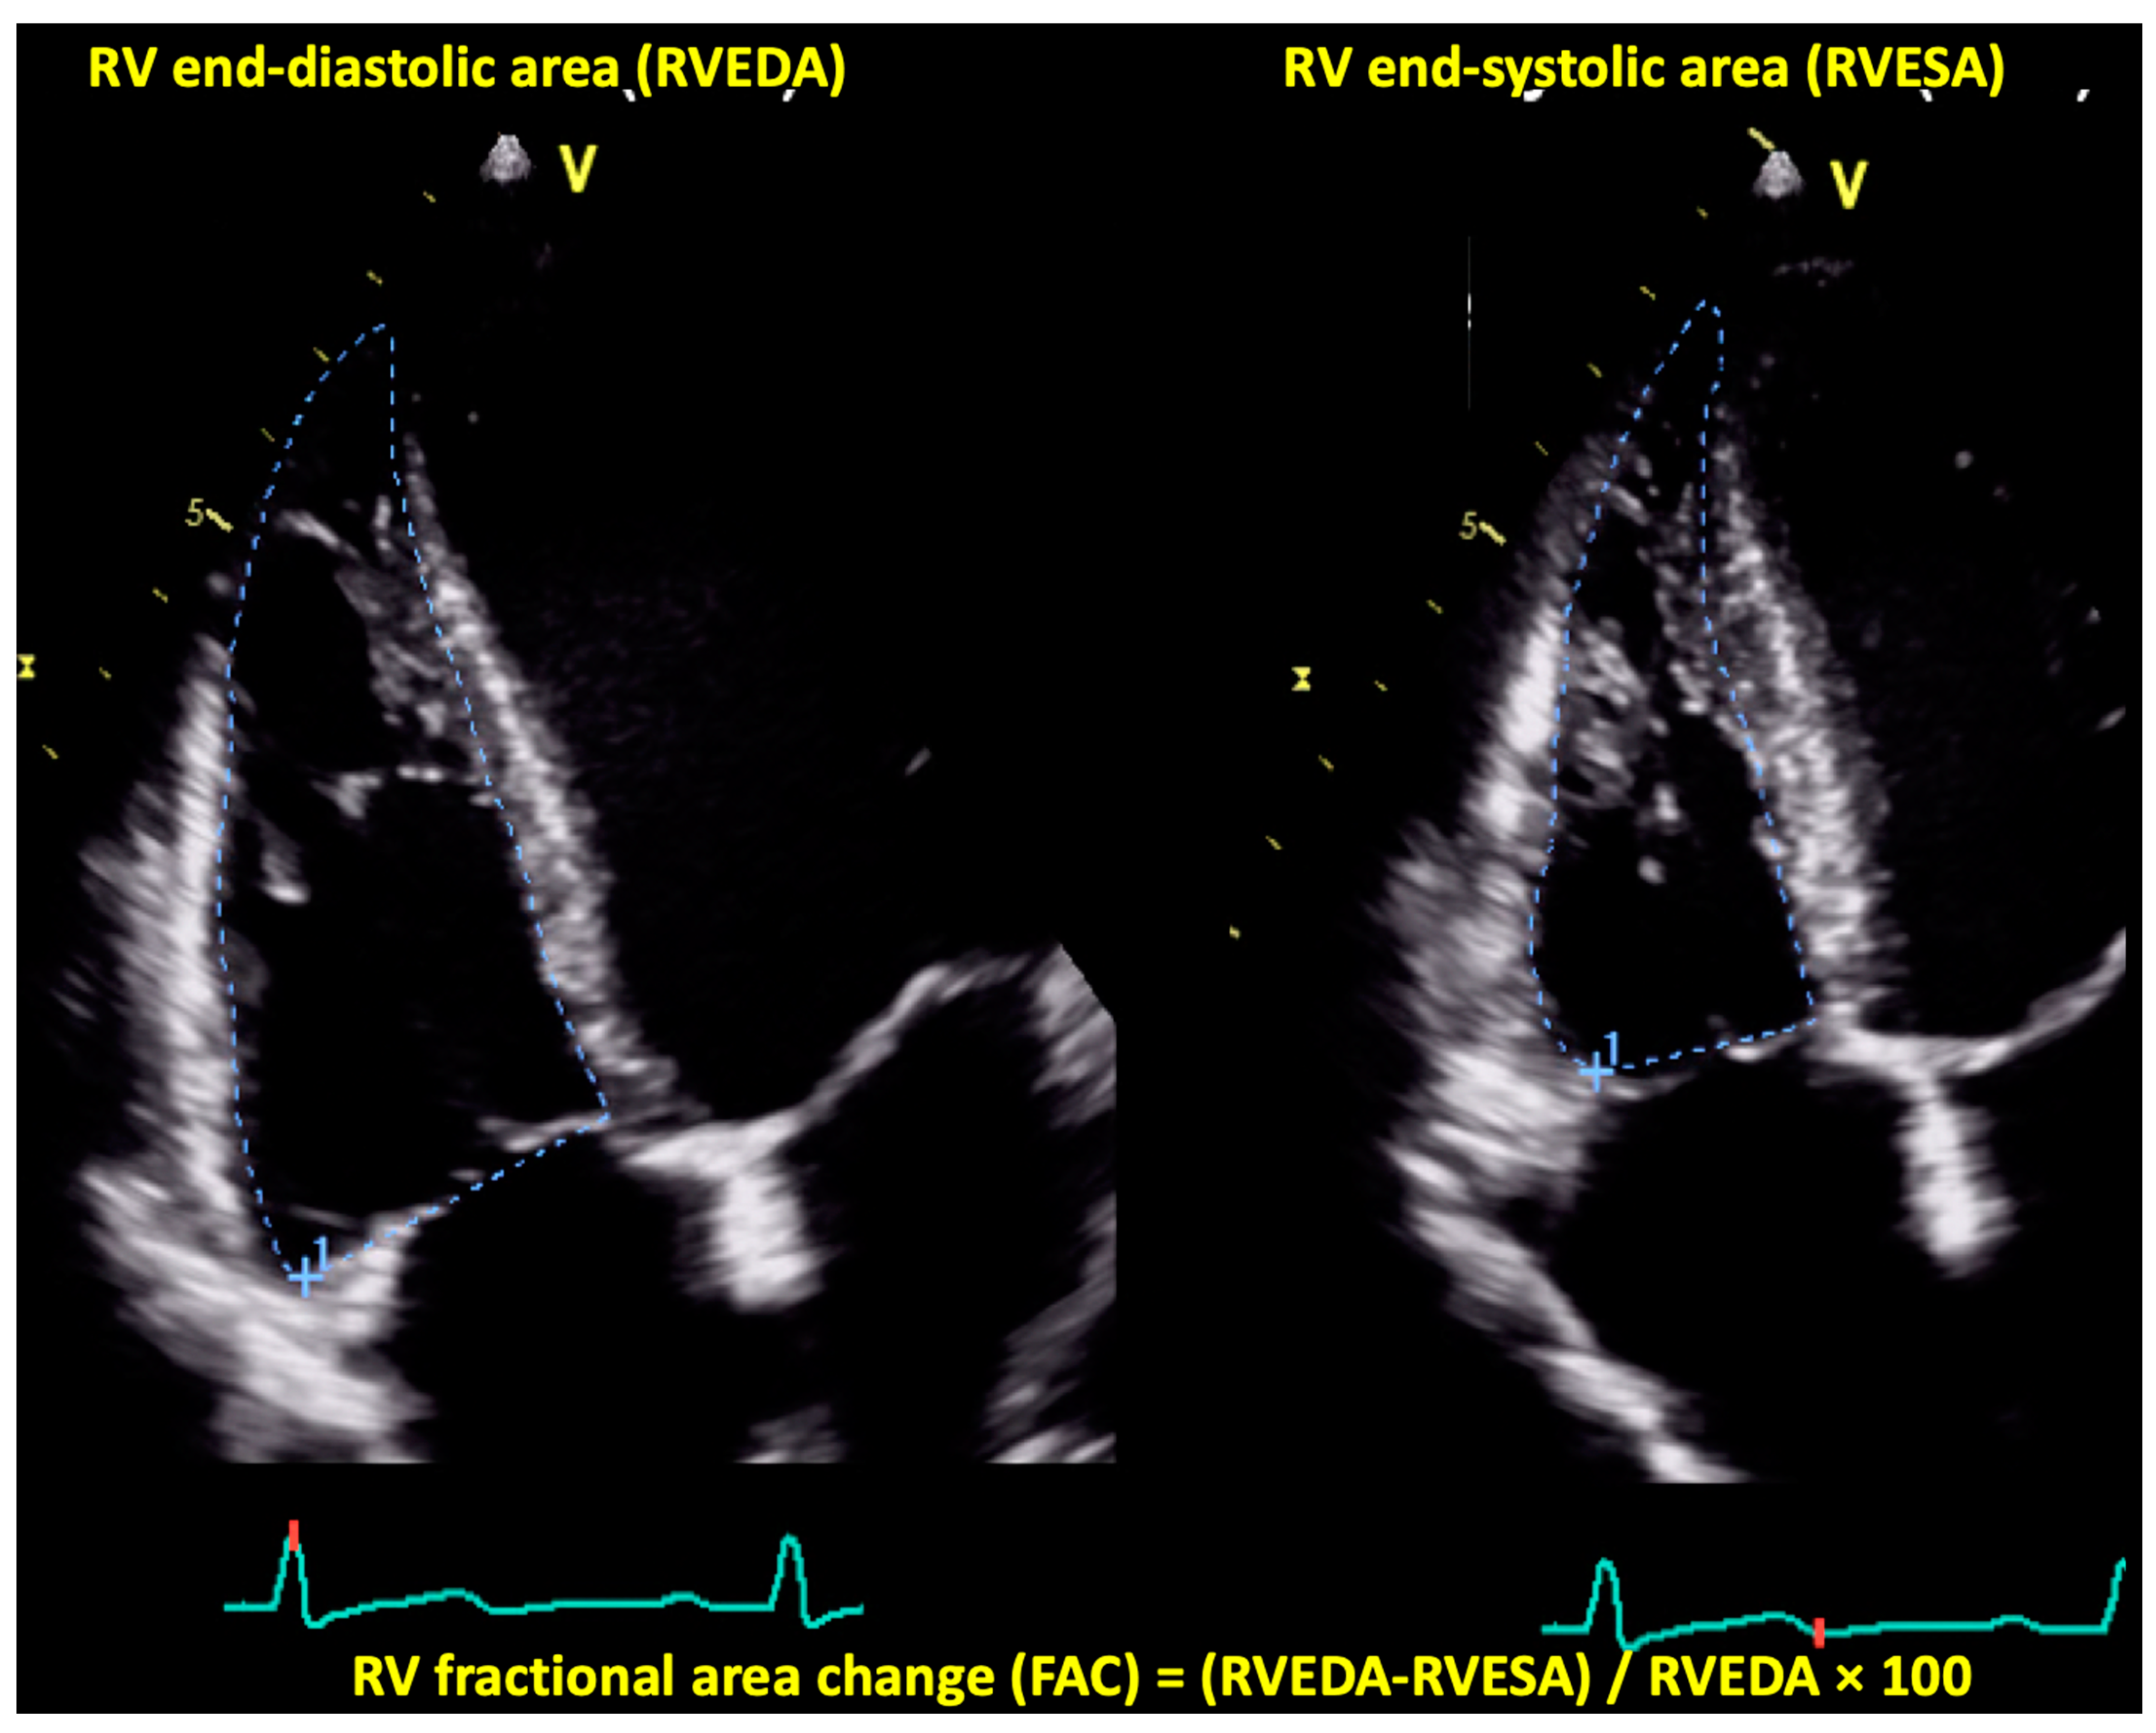

4.1.4. Right Ventricular Fractional Area Change by Two-Dimensional Echocardiography